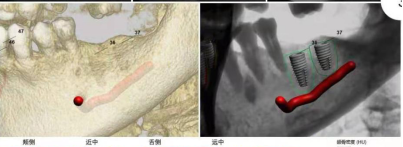

2.为种植提供测量颌骨宽度、长度、密度及各种距离、角度等综合信息,以选择各种种植体尺寸及位置。

3.重要结构的定位,种植体间距离安全碰撞检测(神经管、上颌窦、病变位置等)避免手术中发生突发情况。

4.真实模拟种植体的位置,可选择任意种植型号、大小尺寸等,方便医患直观交流讨论。

5.定制手术外科导板,精确定位种植体位置及方向,提供微创及即刻种植方案